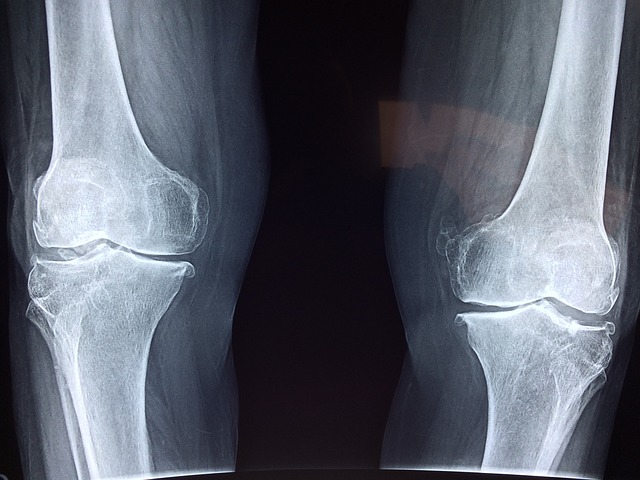

골밀도 검사 부위

골밀도는 일반적으로 골 손실이 발생할 가능성이 가장 높거나 골밀도 측정이 가장 신뢰할 수 있는 신체의 특정 부위에서 테스트됩니다. 골밀도 검사를 위한 세 가지 주요 부위는 다음과 같습니다. 요추와 대퇴부위가 가장 주된 부위입니다. 처음으로 요추입니다. 요추 또는 허리는 나이가 들수록 상당한 뼈 손실이 발생하는 경우가 많기 때문에 골밀도 테스트에 중요한 부위입니다. 요추의 골밀도 측정은 전반적인 척추 건강에 대한 귀중한 통찰력을 제공하고 골다공증을 조기에 발견하는 데 도움이 될 수 있습니다. 다음으로 대퇴 부위입니다. 엉덩이 특히 대퇴골 경부는 골밀도 검사를 위한 또 다른 일반적인 부위입니다. 고관절의 뼈 손실은 이 부위의 골절이 상당한 이동성 문제와 건강상의 합병증을 초래할 수 있기 때문에 주요 관심사입니다. 고관절 검사는 골다공증성 골절이 가장 흔히 발생하는 부위 중 하나의 뼈 강도와 골절 위험을 나타냅니다. 마지막으로 손목입니다. 척추와 고관절보다 덜 일반적으로 검사되지만 손목은 특히 손목 골절이나 기타 뼈 손실 증상이 있는 개인의 경우 골밀도 측정에 적합한 부위이기도 합니다. 손목 골밀도 측정은 잠재적인 문제를 식별하고 적절한 개입을 안내하는 데 도움이 될 수 있습니다.